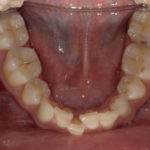

Arcade mandibulaire avant traitement orthodontique, séquelles de maladie parodontale

Après traitement orthodontique et réalisation d’une attelle fibrée (courtoisie Dr Patrick Fournier)